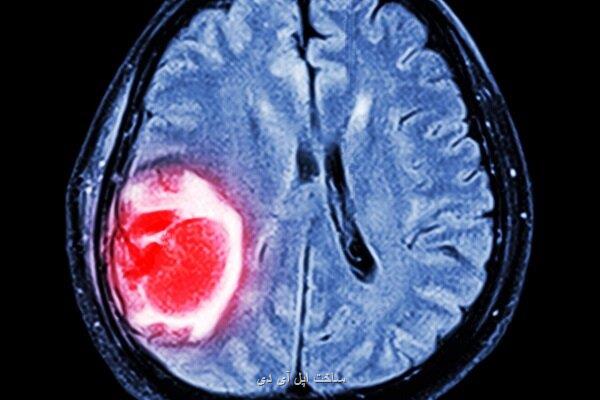

نانوذرات گیاهی با سرطان مرگبار مغز مقابله می کند

نانوذرات گیاهی با سرطان مرگبار مغز مقابله می کند ساخت اپل آی دی: پژوهشگران در چین و آمریکا برای توسعه یک درمان مبتنی بر نانوذرات گیاهی برای گلیوبلاستما (مرگبارترین سرطان مغز) با یکدیگر همکاری کردند.

به گزارش ساخت اپل آی دی به نقل از اینترستینگ انجینرینگ، این نانو ذرات که از فیتوکمیکال (phytochemical)هایی به نام باردوکسولون متیل (BM)ساخته شده اند برای نفوذ به سد خونی- مغزی و هدف گرفتن سلول های تومور بطور مستقیم طراحی شده اند. فیتوکمیکال ها مواد بیواکتیو گیاهانی هستند که بر طبق ساختار شیمیایی و عملکرد فیزیولوژی گروه بندی شده اند. پژوهشگران دانشگاه رمنین ووهان و دانشگاه یل این نانوذرات را به موش ها تزریق و مشاهده کرد آنها بطور موفقیت آمیز سلول های تومور را شناسایی و به آنها حمله کردند. درمان فعلی این نوع از سرطان مغز شامل جراحی حذف تومور است. بعد از این پروسه بیمار باید اشعه درمانی و شیمی درمانی انجام دهد اما سرطان ممکنست با وجود درمان مقاومت کند. در نتیجه تاثیر درمان بر بیماری اندک خواهد بود. یک چالش مهم دراین زمینه سد خونی-مغزی یا غشای حفاظتی دور مغز است. خیلی از داروها از این مانع رد نمی شوند و تاثیرگذاری آنها بر درمان بیماری هایی مانند گلیوبلاستوما اندک خواهد بود. نانو ذرات تازه توسعه یافته می تواند این چالش را برطرف کند. طبق مطالعه مولکول های گیاهی این درمان ذراتی ریز به وجود می آورند. این مواد بسیار ریز و حدود ۵۰ تا ۸۰ نانومتر قطر و ۱۷۰ نانومتر طول دارند.